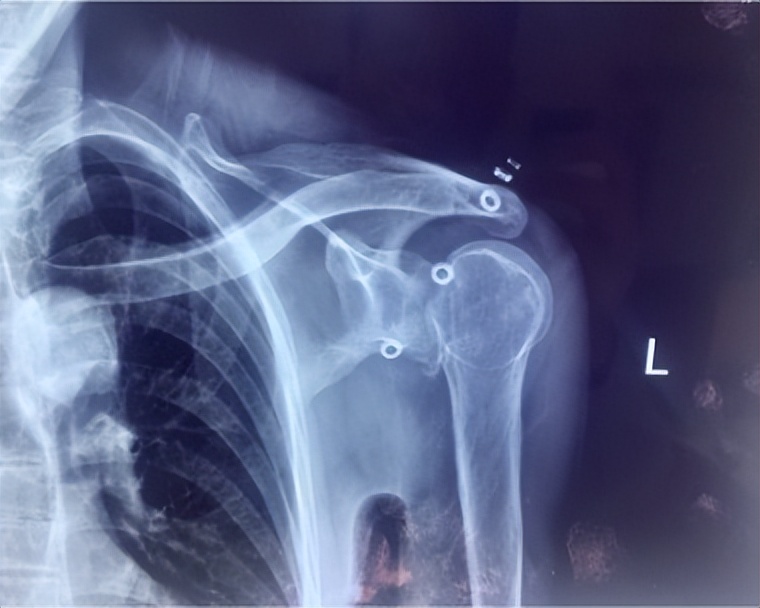

面对这例受伤时间长、脱位类型少见、骨折情况复杂的患者,创伤中心常务副主任李连欣组织全科病例讨论,通过分析认为该患者为“陈旧性绞锁性肩关节后脱位合并肱骨头骨折(反Hill-Sachs损伤)”,患者疼痛活动障碍,不能继续保守治疗,需要进行手术。患者的手术难点在于:患者为陈旧性后脱位,周围组织已经严重粘连、僵硬;脱位的肱骨头卡于关节盂造成关节面缺损,很难恢复肱骨头原本的解剖结构;合并肩袖巨大陈旧性撕裂,难以修复;患者为老年,骨质疏松明显;病程长达10年,即使手术勉强恢复其解剖关系,未来发生肱骨头缺血坏死、创伤性关节炎等并发症的几率极高。经过科室充分讨论分析,最终确定反式肩关节置换的手术方案。

肩关节脱位俗称脱臼,是临床常见损伤,后脱位少见,仅占肩关节脱位的2%, 合并肱骨近端骨折的罕见,其发病因素主要是外伤*力暴**及骨质疏松。一般临床上把骨折脱位时间在三周以上的称为陈旧性骨折或脱位。对于肩部脱位多数可以手法复位获得较好效果,新鲜骨折通过手术复位固定一般也可获得满意的效果,但对于陈旧性脱位或骨折,由于关节的挛缩、粘连等,骨折断端和周围存在大量瘢痕组织和骨痂,时间再长即导致畸形愈合,复位十分困难,也难以实施内固定。实施关节置换也存在软组织不平衡,脱位,神经损伤等风险,手术很有挑战性。